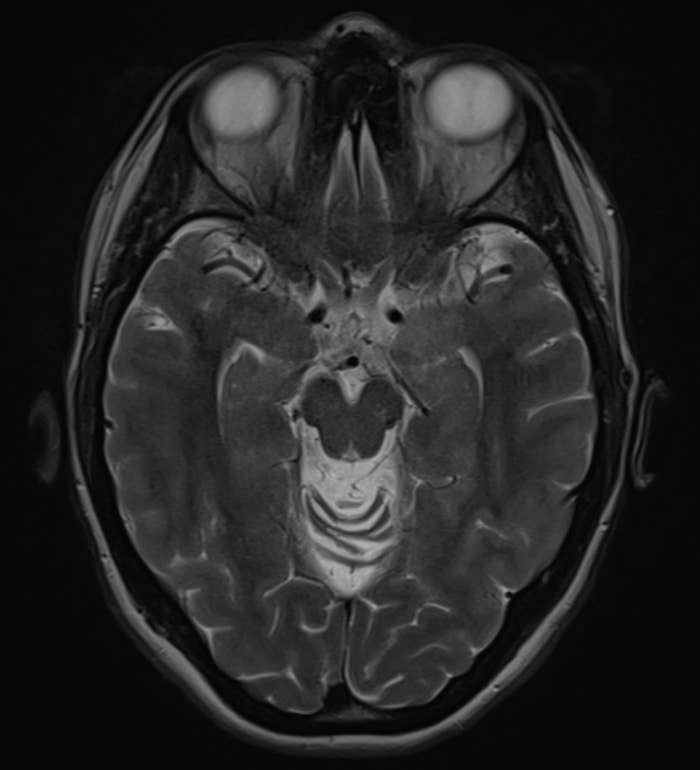

Neurologists Are Opening Up About Sleep Problems That Might Be Warning Signs Of Dementia

Experts reveal which sleep disturbances may signal something deeper, and when you should be concerned. This article originally appeared on HuffPost.